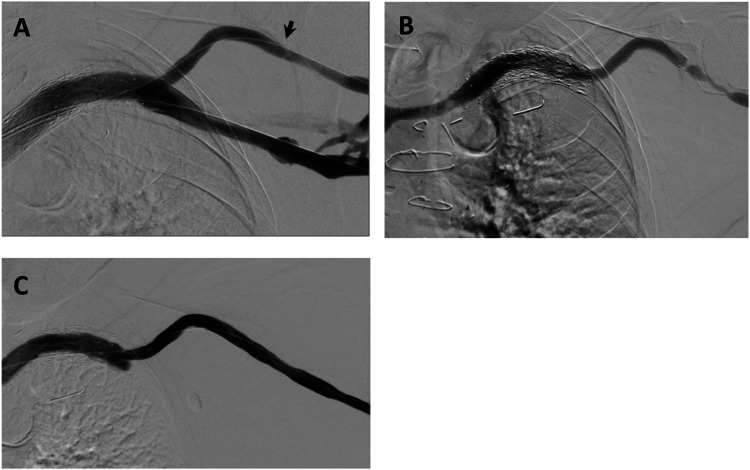

目的描述西澳大利亚一家三级医疗中心使用 WRAPSODY 细胞防渗内支架的临床效果:使用 WRAPSODY 治疗动静脉通路静脉外流顽固性闭塞疾病患者。对患者进行前瞻性随访,直至术后 12 个月。研究指标包括 30 天不良事件、技术成功率、靶病变主要通畅率、通路主要通畅率和辅助通路主要通畅率:结果:共使用 27 台 WRAPSODY 设备治疗了 15 名连续患者。技术成功率为 100%。随访期间未发现与设备相关的不良事件。两名患者未完成全部随访。3个月、6个月和12个月的靶病变主要通畅率分别为100%(15/15)、100%(15/15)和100%(13/13)。3个月、6个月和12个月时通路原发性通畅率分别为73.3%(11/15)、46.7%(7/15)和46.2%(6/13)。在 33.3%(5/15)的病例中观察到边缘狭窄,在血管造影显示通路初级通畅失败的 8 位患者中,有 5 位是边缘狭窄。12个月后,初级辅助功能通畅率为100%:结论:在现实世界中,WRAPSODY 可以安全地用于解剖结构复杂的肾脏通路狭窄病变患者,并具有持久的通畅性。与该装置相关的治疗优势可能会鼓励在临床实践中更广泛地使用该装置。

ObjectiveTo describe clinical outcomes associated with the use of the WRAPSODY Cell-Impermeable Endoprosthesis at a tertiary center in Western Australia.MethodsPatients with recalcitrant occlusive disease in the venous outflow of their arteriovenous access circuits were treated with WRAPSODY. Patients were prospectively followed up to 12-month post-procedure. Study measures included 30-day adverse events, technical success, target lesion primary patency, access circuit primary patency, and assisted access circuit primary patency.ResultsTwenty-seven WRAPSODY devices were used to treat 15 consecutive patients. The technical success rate was 100%. No device-related adverse events were observed during the follow-up period. Two patients did not complete the full follow up. Patency rates at 3-, 6-, and 12 months for target lesion primary patency were 100% (15/15), 100% (15/15), and 100% (13/13), respectively. Rates for access circuit primary patency at 3-, 6-, and 12 months were 73.3% (11/15), 46.7 % (7/15), and 46.2% (6/13), respectively. Edge stenosis was observed in 33.3% (5/15) of cases and accounted for 5 of the 8 patients who experienced failed access circuit primary patency on angiogram. Primary assisted functional patency was 100% at 12 months.ConclusionWRAPSODY can be utilized safely and has durable patency in real-world patients with complex anatomical renal access stenotic lesions. The therapeutic benefits associated with the device may encourage broader use in clinical practice.